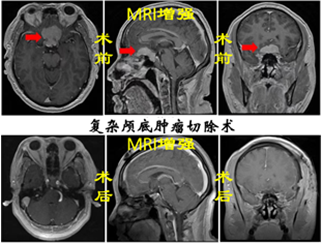

神經腫瘤:神經腫瘤作為神經系統疾病中最為棘手的疾病之一,常見的有膠質瘤、腦膜瘤、垂體瘤、神經鞘瘤、轉移瘤、先天性腫瘤等,手術方式包括超聲導航+熒光造影引導下腦腫瘤切除術、鞍結節腦膜瘤切除術等,借助顯微鏡等先進設備,在保留正常腦組織的情況下,最大程度切除腫瘤組織,為患者爭取后續康復機會。

7301b9c9b7144d69bb38c6a635a3f512.Png6efcf3a55301466dbf75113390793f2e.Png